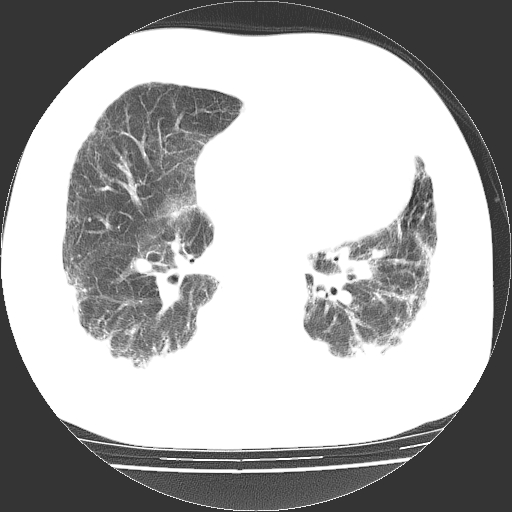

依据:1、两肺广泛条索状、网格状、蜂窝状改变。

根据3天的病史考虑 肺部感染,间质肺炎可能性大,网格及蜂窝影提示病灶时间较长结合肺纹混乱支持慢支炎,肺间质纤维化,肺心病,双侧胸腔积液。抗炎治疗复查

双肺多发条索状、网格状及小灶状密度增高影。考虑慢支合并感染.间质纤维化,双侧少量胸腔积液

两肺广泛条索状、网格状、蜂窝状改变。肺间质纤维化,肺心病,双侧胸腔积液